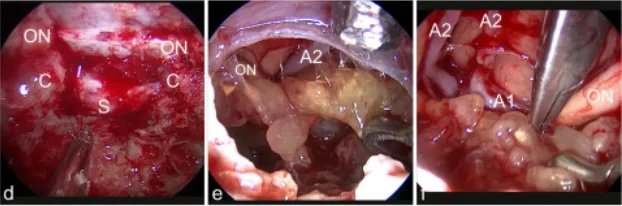

d图中,肿瘤(T)为通过右侧额外侧入路,暴露右视神经(ON)e图中,肿瘤包膜是用刀切开,f图显示钙化的肿瘤部分已被肿瘤切除

g图中,使用镊子的双向牵拉技巧解剖分离肿瘤;h图中,肿瘤(T)在30°神经内窥镜视野下正常显微镜难以显示;i图中,最终检查显示肿瘤全切除和视神经完整保留(ON)